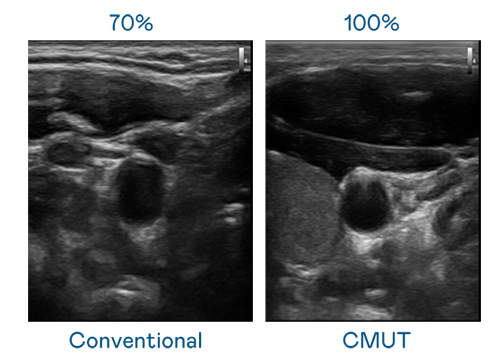

CMUT 技术是一种用电容式微机电元件来产生超音波讯号的技术。与传统 PZT 压电式技术相比,CMUT 频宽增加 30%,更宽频的超音波讯号让影像解析度大幅提升,是实现高影像品质医疗超音波扫描、促进精准医疗发展的关键技术。

大频宽带来超清晰影像

超音波影像的解析度高低,首先取决于探头能发出的讯号频宽。云顶国际 CMUT 可提供高清晰的超音波讯号,提供高频宽、高灵敏度、影像纹理细节更高的超音波影像,协助医护人员缩短影像判读时间及利用精准的医疗影像进行诊断。